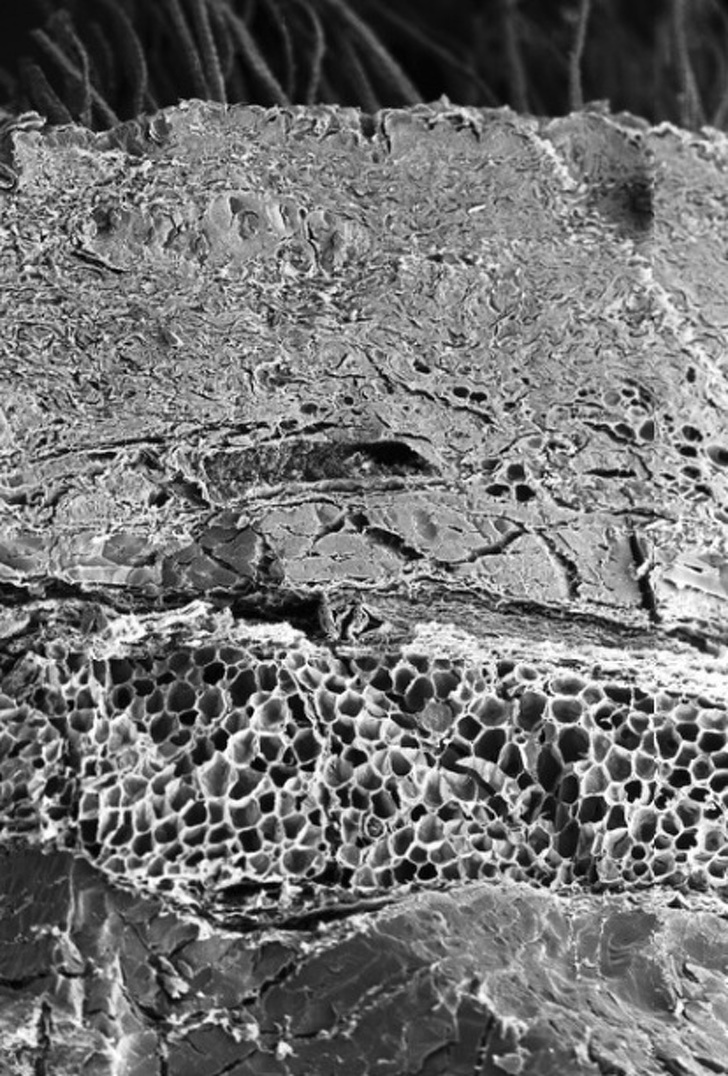

Кістка